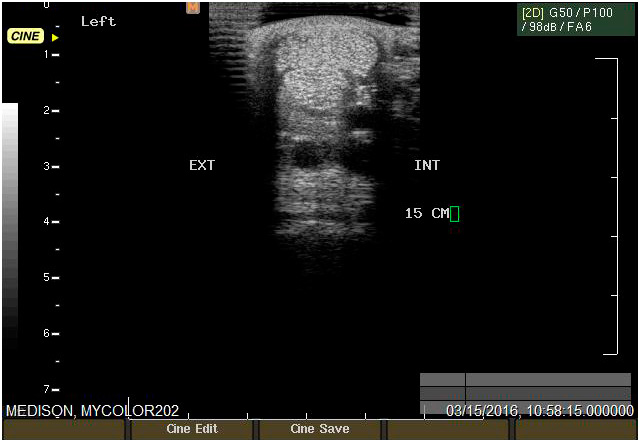

Ecografía

Cuenta con Ecografía digital de alta complejidad.

17 años de experiencia siendo una de las ecografistas más reconocidas en la práctica de equinos. Realiza pasantías en la universidad de Davis California y en Mid-Atlantic Equine Medical Center en New Jersey.